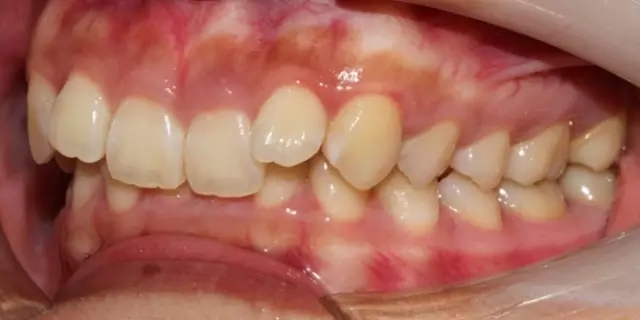

Damon 病例分享:安氏 II 類(lèi)二分類(lèi)露齦笑的矯治(董一磊)

患者信息

治療前后對(duì)比